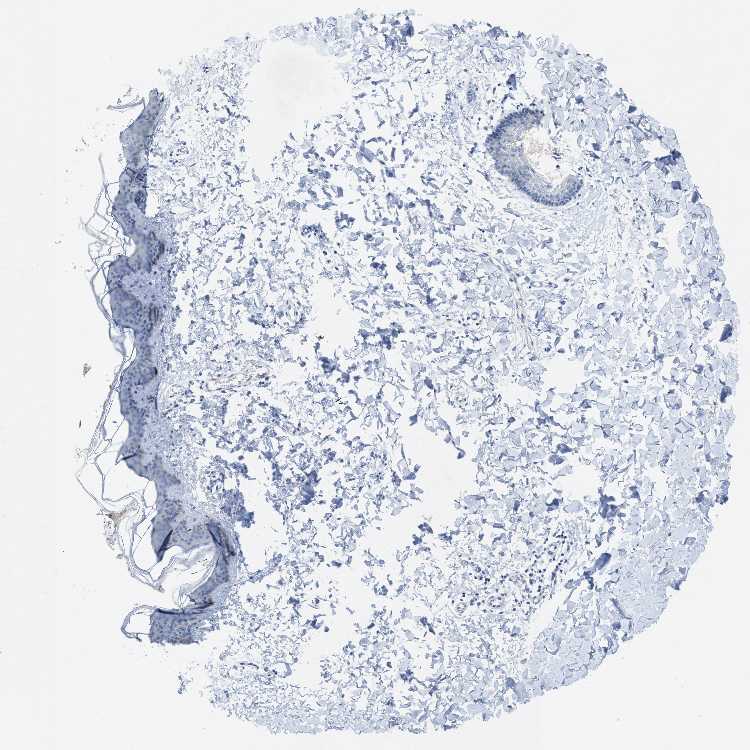

SKIN 1 - Antibody stainingi

Antibody staining in the annotated cell types in the current human tissue is reported as not detected, low, medium, or high, based on conventional immunohistochemistry profiling in selected tissues. This score is based on the combination of the staining intensity and fraction of stained cells.

Each image is clickable and will lead to virtual microscopy that enables deeper exploration of all samples and also displays staining intensity scores, fraction scores and subcellular localization as well as patient and tissue information for each sample.

Antibody HPA013801Antibody HPA017136

Langerhans Not detectedNot detected

Fibroblasts Not detectedNot detected

Keratinocytes Not detectedNot detected

Melanocytes Not detectedNot detected